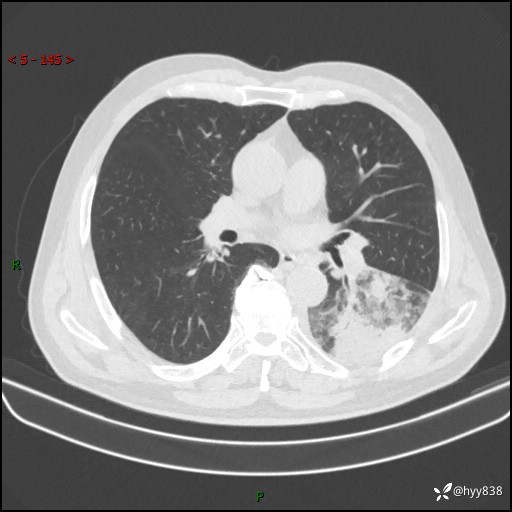

59岁/男,发热伴咳嗽3天。白班偶遇,“大叶性肺炎”,病原体挑战---结果公布~

【患者信息】:59岁/男

【主诉】:发热伴咳嗽3天

【现病史及既往史】:患者3天前无明显诱因出现发热,体温最高达38.6℃,伴有咳嗽,干咳为主,感乏力、肌肉酸痛,无明显头晕头痛、鼻塞、流涕、呼吸困难、胸痛、恶心呕吐、腹痛腹泻、尿频尿急等不适,于当地诊所输液治疗3天感症状无好转,仍有间断发热、咳嗽,现为求进一步诊治,于我院门诊就诊,门诊以“发热待查”收入我科进一步诊治。 患者自发病以来,精神、饮食、睡眠欠佳,大小便正常,体力、体重无明显变化。

【检查】:胸部CT平扫